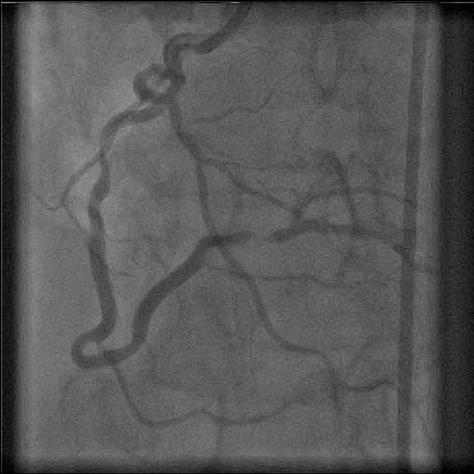

One or more bends of 90° or more, or three or more bends of 45° to 90° proximal of the diseased segment.